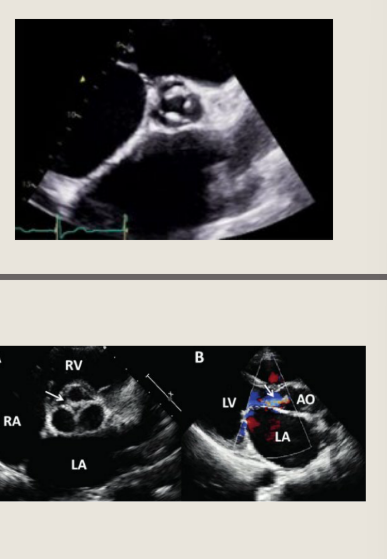

VSD with Aortic Prolapse

Define in systole and what effect is this known as?

In early systole (left), blood ejected from the

left ventricle will be shunted through the

ventricular septal defect

The unsupported right coronary cusp and

right aortic sinus are driven into the right

ventricle. This limits left to right shunting of

VSD flow

This is known as the Venturi effect

in diastole

This is best evaluated in what view

In diastole (right), the intra-aortic pressure

forces the aortic valve leaflet to close, but

the unsupported right coronary cusp is

pushed down into the left ventricular

outflow tract away from the opposed

coronary cusp, resulting in regurgitation

This is best evaluated in PLAX